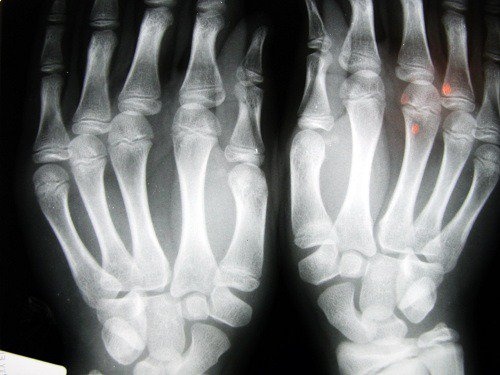

Риск от остеоартрит

Изследване, направено от Универстита в Нотингам, Англия, установи, че хората с по-къс показалец са изложени на по-висок риск от развитие на здравословни проблеми като остеоартрит. Това заключение се дължи на факта, че при тях се открива ниско ниво на естрогена и ниска физическа активност. Остеортритът обикновено застига жените.